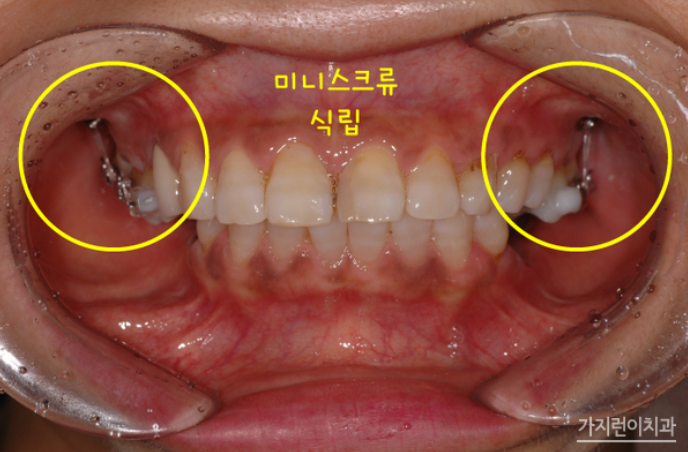

먼저 환자분의 케이스는 하악 구치부의 결손이 발견 되었고 잇몸 퇴축 현상이 일어나면서 추후 임플란트 진행이 어려울 가능성도 있어 치료를 통해 미니스크류를 이용한 치아교정과 임플란트를 동시에 진행하게 되었습니다.

위 사진을 보면 미니스크류를 이용해 상악 구치부의 함입을 위해 충분히 힘이 갈 수 있도록 진행을 도왔습니다. 바깥 부분의 안쪽에 미니스크류를 식립해 상악 구치부의 함입을 달성할 수 있게 했는데요. 여기에 상악 전치의 뻐드렁니를 개선하고 하악의 작은 어금니를 발치했다는 가정을 세운 후에 치료를 진행했습니다. 원래대로라면 모두 6개의 임플란트 식립이 필요한 상황이었지만 이 가정으로 치료플랜을 세웠을 때 임플란트를 4개만 심을 수 있었는데요.